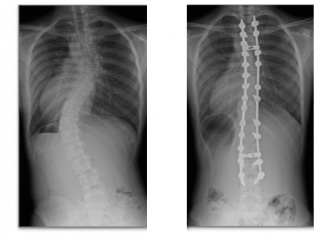

特発性側弯症

基礎疾患のない側弯症で女児に多く、日本人での発生率は2~3%とされます。進行するリスクが高い症例ではまず装具治療を行います。ある程度以上に進行すると骨成熟後も悪化するため、手術が必要になります。

装具治療

手術治療